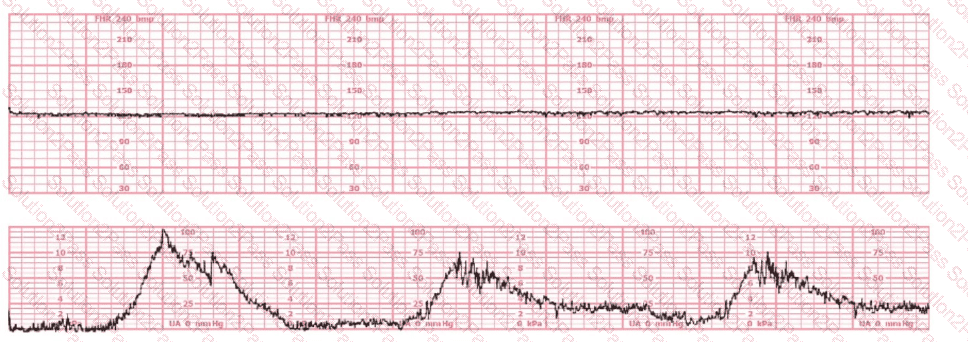

The pattern on the fetal heart rate tracing shown is likely due to

The fetal heart rate tracing shown demonstrates:

The tracing shown is a:

A 20-year-old woman (G1P0) at 40-weeks gestation was admitted for cervical ripening with dinoprostone (Cervidil) four hours ago. She developed the pattern shown one hour ago. She has been changed to a lateral position and given a fluid bolus, and the pattern continues. An appropriate intervention would be to: